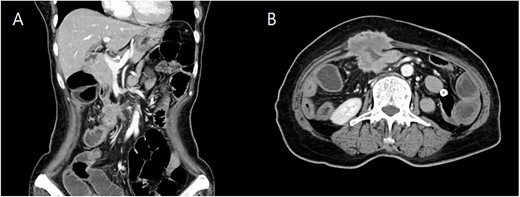

She underwent computed tomography (CT), which showed focal wall thickening at the transverse colon with direct invasion to the rectus muscle and subcutaneous fat layer of the anterior abdominal wall (Fig. 2). The surrounding multiple small lymph nodes were suspected of metastasis. There was another 2-cm tumor lesion in the sigmoid colon. She was diagnosed locally advanced transverse colon cancer and early sigmoid colon cancer after colonoscopy and biopsy.

Coronal (A) and axial (B) computed tomography image of abdomen and pelvis showing transverse colon cancer with direct invasion to the rectus muscle and suspicious invasion of superior mesenteric invasion.